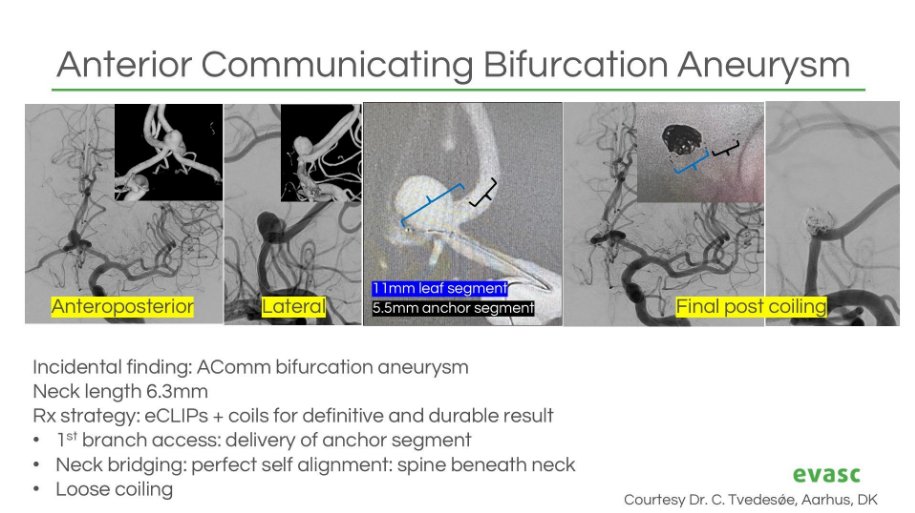

Treating wide-neck bifurcation #aneurysms? #eCLIPs could be the solution. Join Dr. Jan-Hendrik Buhk in this ESMINT Society webinar on how eCLIPs works + where it fits in complex cases. Watch: esmint.eu/video/wide-nec… For more information: bit.ly/contact-evasc or DM us.

Real-world data confirm #eCLIPs delivers durable, efficient & safe outcomes for #WNBAs — now published in Neurosurgery Publications . Plus: CE/MDR approval & limited launch of our 0.021" compatible eBFD. 📄 Study: bit.ly/4lezYWp 🔗 PR: bit.ly/41oko3f #Neurointervention